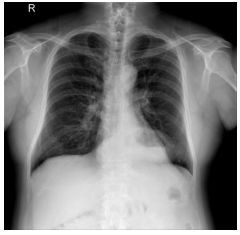

4. 39 y/o female, productive cough for 2 months